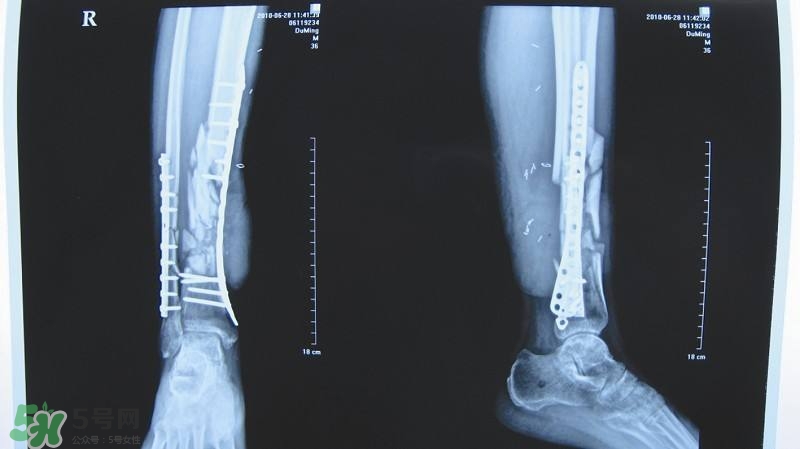

1、X線照片顯示骨折線模糊,有連續(xù)性骨痂通過骨折線;